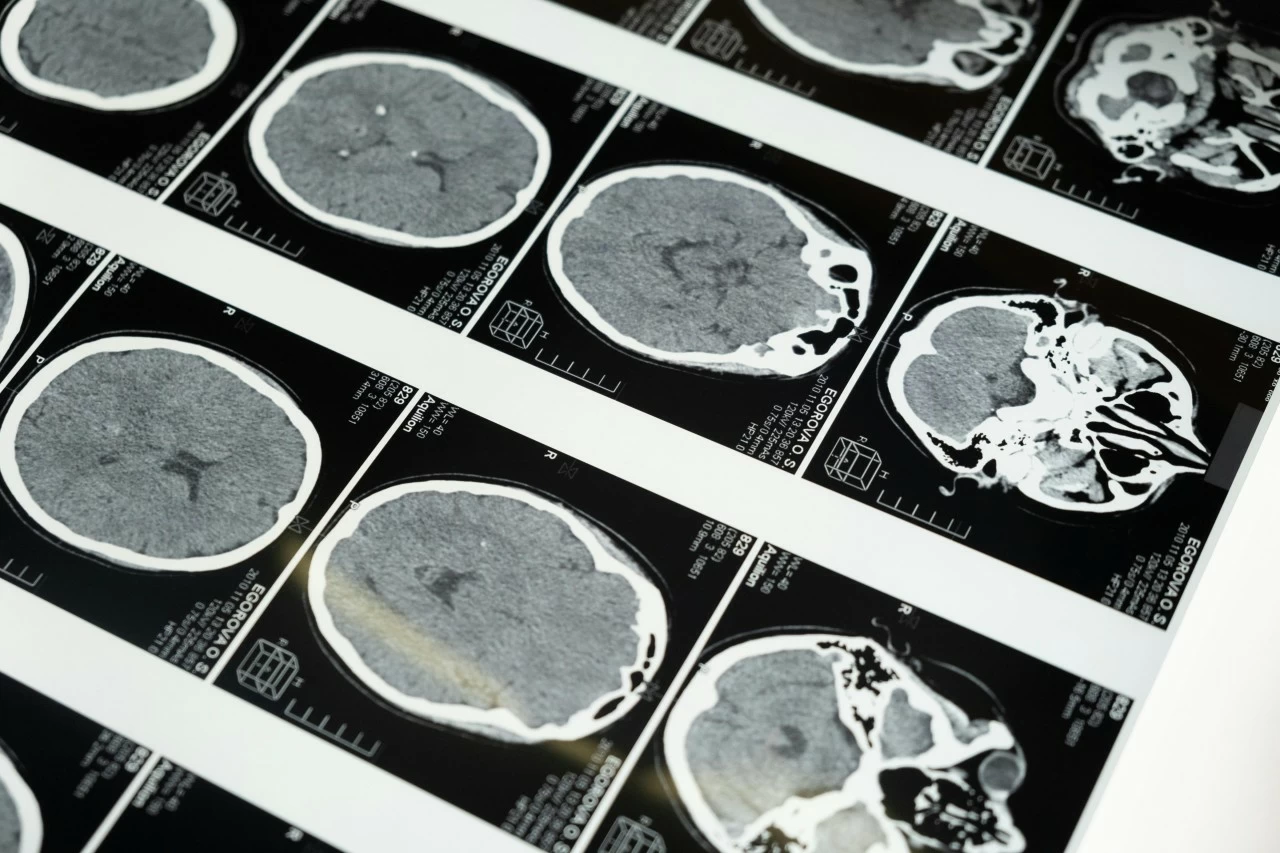

The team examined MRI scans from 3,802 individuals ranging from childhood to 90 years old, using specialised imaging that tracks the movement of water molecules in brain tissue. This method allowed scientists to monitor subtle changes in white and grey matter — the networks that enable learning, memory, movement, and decision-making. The researchers identified four key turning points in brain development and deterioration: ages 9, 32, 66, and 83.